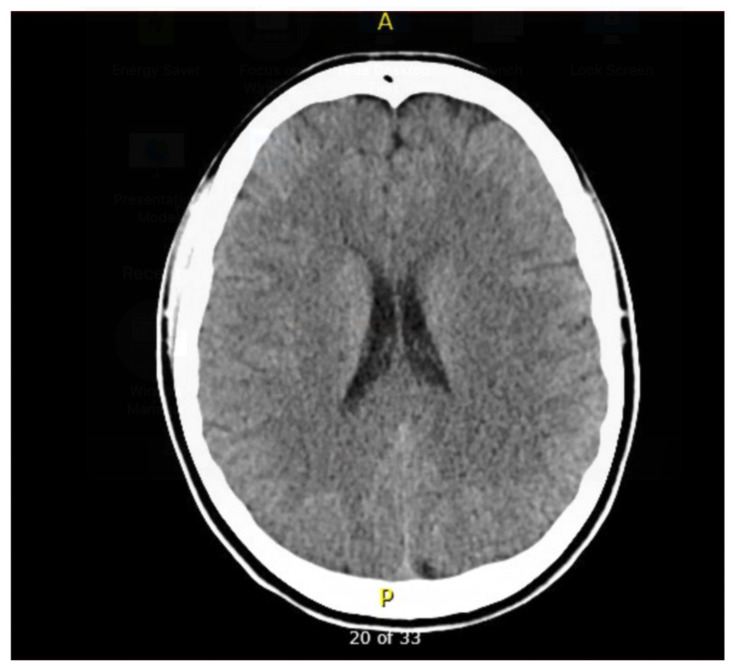

Next, the learner must formulate a prioritized differential diagnosis that includes both common and life-threatening etiologies of altered mental status in a young woman (Objective 2). Based on their assessment and differential, the learner will be required to select appropriate diagnostic studies and accurately interpret key clinical data, including laboratory values, urinalysis, ECG, imaging, and point-of-care tests (Objective 3). The diagnostic results in this case include leukocytosis, a nitrite-positive urinalysis, a normal glucose level, a normal head CT, and a suppressed thyroid-stimulating hormone (TSH) with elevated T3 and free T4. An ECG is provided that shows atrial fibrillation with rapid ventricular response, which the learner must recognize and incorporate into their diagnostic reasoning.

| 5 | Able to provide three findings on a head CT that would cause altered mental status | ||

| #7 | Head CT |